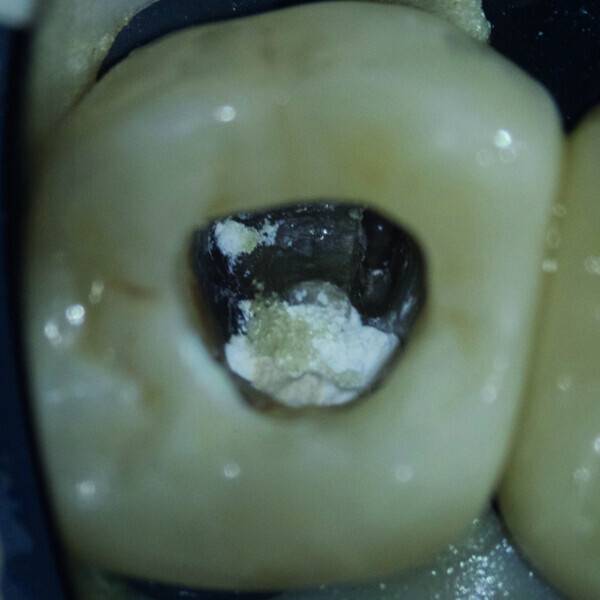

Fig. 6 : Le ciment hydraulique à base de silice après sa prise complète.